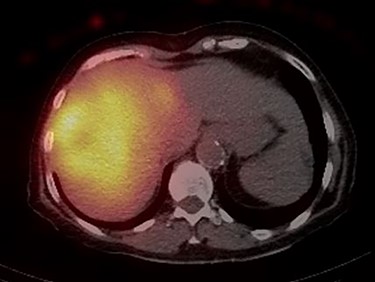

Post-treatment dosimetry done using the Bremsstrahlung liver SPECT image and the Sure Plan software demonstrated that the mean dose delivered to the main right liver lobe tumor (GTV) was 156 Gy. Ninety-five percent of the GTV received 108 Gy with a max dose of 213 Gy. The mean dose to the Segment IVA lesion was only 62 Gy, with 95% of the lesion receiving 36 Gy (Figs 8 and 9).

Axial and coronal views of the Y-90 dose distribution; the majority of the uptake is within the GTV with minor uptake in the Segment IVA lesion.